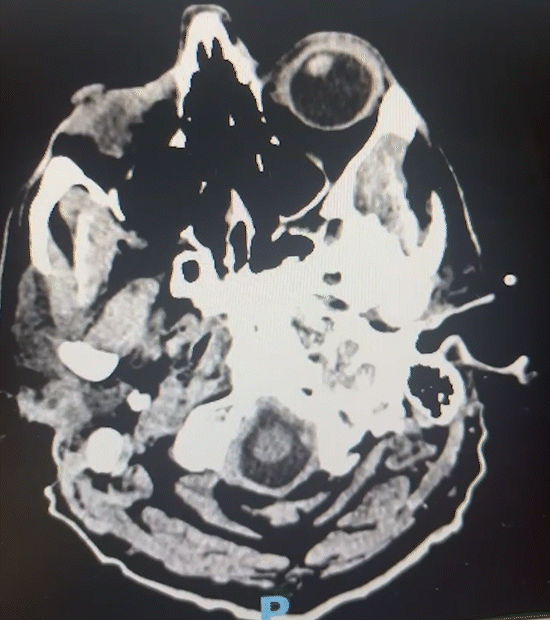

Post operation MRI

Pre-operation brain tumor MRI

One of Dr. Babu’s patients underwent surgery for a brain tumor and experienced an excellent recovery. Following the procedure, the patient shared this heartfelt message:

Before-and-after MRI scans confirmed the successful removal of the tumor. Today, the patient is recovering well and regaining quality of life thanks to expert surgical care and attentive follow-up.